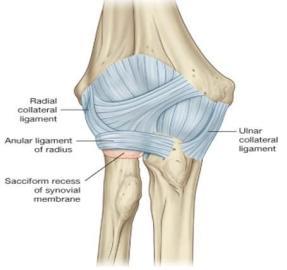

Discuss the stability of elbow joint

Describe the anatomical position of the collateral ligaments of the elbow joint